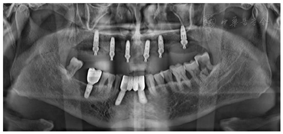

影像学检查:曲面体层片及根尖片示13、16、42、38、48牙槽骨吸收至根尖;剩余牙牙槽骨吸收至根长1/2。CBCT示上颌正中多生牙,多生牙舌侧可见不规则低密度影像。(图2、图3)

①阿替卡因肾上腺素注射液局麻下拔除13、16,制作上颌过渡性总义齿。②治疗方案设计:拟在12、14、16、22、24、26植入6颗种植体(图4),术前制作种植导板。③13、16牙槽窝愈合6周后,行种植一期手术:16-26牙槽嵴顶全层翻瓣,导板定位定点,16、14分别植入Nobel PCC 4.3 mm×11.5 mm种植体,12、22分别植入Nobel PCC 3.75 mm×11.5 mm种植体,24植入Nobel PCC 4.3 mm×10 mm种植体,26上颌窦外提升植骨,6个月后行种植一期手术,植入Nobel PCC 4.3 mm×10 mm种植体(图5、图6)。④种植二期手术:12、22放置NP30°3.5 mm复合基台;14、24放置RP30°3.5 mm复合基台;16、26放置RP17°3.5 mm复合基台(图7),复合基台均加力至15Ncm。⑤制取种植印模:去除12、14、16、22、24、26复合基台保护帽,放置开口式印模柱,结扎丝连接,3M冠桥树脂固定,制取开口式硅橡胶印模,灌注模型(图8、图9)。